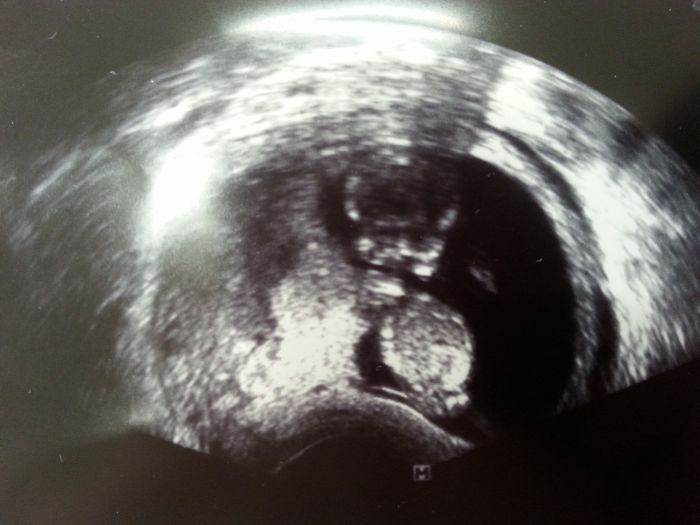

Ahojky holky, dneska mě začala strašně bolet jedna ledvina. Učitelka mě poslala okamžitě k lékaři. Udělala se prohlídka která by se dělala v pátek. Miláčkovi krásně buší srdíčko, máme 5,2 cm. :) a odpovídáme přesně 12tt+2 . :) termín mám mát teda definitivně 3.8 :) UTZ mi doktor ještě dělal spodem, aby toho bylo vidět víc. :) držím vám palečky, já teďka budu 4 týdny čekat na další prohlídku :D

abych tady taky napsala něco hezkého...tak po dnešním screeningu je vše v pořádku (měli volat do 15:00 kdyby něco bylo). Medvídek se měl k světu. Vrtěl se, slyšeli jsme srdíčko, je zase o kus větší. Tak těm co to čeká zítra a později, tak si to užijte.

Příkládám fotku :)